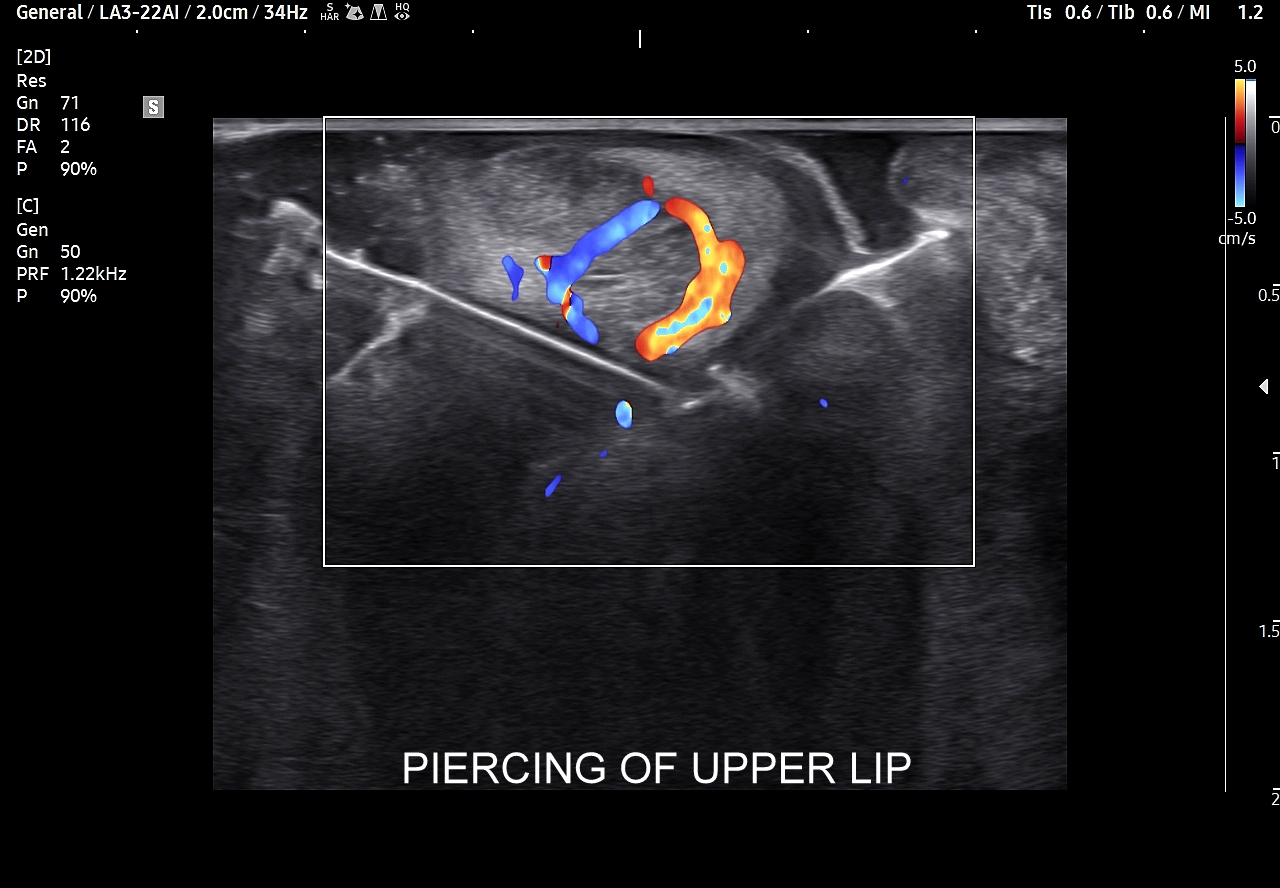

W kontekście powikłań żylnych związanych z trójkątem śmierci należy wspomnieć o zagrażających życiu powikłaniach wstępujących pod postacią zakrzepowego zapalenia zatoki jamistej i głębszych zatok wewnątrzczaszkowych skutkujących obrzękiem mózgu. Poprzez układ żylny oraz tętniczy rozprzestrzeniać mogą się również powikłania infekcyjne, których przykładem są zapalenie opon mózgowo-rdzeniowych i ropień mózgu. Źródłem powikłań infekcyjnych są zapalne stany skóry i tkanki podskórnej w obrębie twarzy oraz trójkąta śmierci, takie jak czyraki i ropnie. Z kolei powikłania zakaźne zstępujące to przede wszystkim infekcyjne zapalenie wsierdzia, zapalenie płuc, czy septyczna zatorowość płucna. Powikłania te związane mogą być również z modnym wśród młodzieży z piercing’iem nosa i warg.

Trójkąt śmierci na twarzy obejmuje również usta. Należy pamiętać, iż są one organami mocno unaczynionymi, co przedstawione jest na załączonych obrazach sonograficznych, a wszelkie infekcje ostre bądź przewlekłe, spontaniczne lub jatrogenne również mogą być przyczyną w/w infekcyjnych powikłań wstępujących oraz zstępujących.